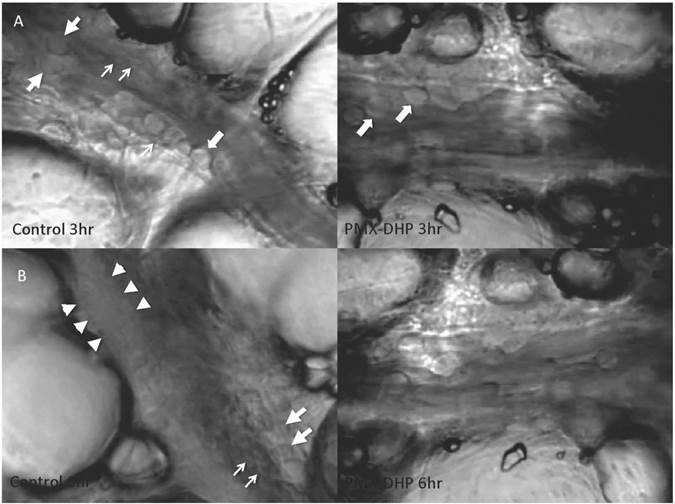

At three hours after LPS instillation, leukocyte adhesion to the endothelial surface of the venule was observed in both the control and the PMX-DHP groups. In addition to leukocytes, platelets had stuck to the endothelium and leukocytes in the control group, whereas, minimal sticking was observed in the PMX-DHP group (Fig. 1A). These changes increased over time, and the lining consisted of adherent leukocytes and platelets covering the surface. As a result, the vascular lumen became significantly narrow at six hours in the control group. Although the number of leukocytes increased, the lining was not observed in the PMX-DHP group and the blood flow was better maintained (Fig. 1B).

Fig 1

Status of lung microcirculation at 3 and 6 hours after LPS inhalation. At 3 hours (row A), in addition to the adherent leukocytes (large arrows), platelets had stuck to the endothelium and leukocytes (small arrows) in the control group (left). Leukocytes, but very few platelets, adhered to the endothelium in the PMX-DHP group. (Objective lens with a magnifying power of ×20). At 6 hours (row B), a thick lining formed from adherent leukocytes, platelets and fibrin deposition (between the arrowheads) had narrowed the vessel cavity in the control group. The large arrow indicates a leukocyte, and the small arrows indicate platelets. Blood flow was maintained in the PMX-DHP group. (Objective lens with a magnifying power of ×20)